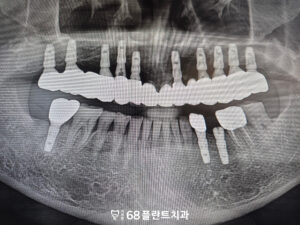

위쪽에 전체적으로

식립이 이루어졌기 때문에

교합의 균형과 식립 각도, 깊이를

더욱 정밀하게 고려해야 했습니다.

이후 치유가 안정적으로

진행된 것을 확인한 뒤에는

보철 제작을 위한 인상 채득 후

위,아래 관계를 정밀하게 분석하여

전체적인 저작 균형을 맞추는 데

중점을 두었습니다.

이후 제작된 보철물을 시적해 보며

적합도와 교합, 심미적인 부분까지 점검한 뒤

최종적으로 연결하여

기능적·심미적 회복을

마무리하였습니다.

그리고 아래쪽 역시 치아를 발치한 후

치료 계획에 따라

임플란트를 식립하였습니다.

이후 치유 기간을 거치고

임플란트가 잇몸뼈에 잘 결합되어

보철 작업을 진행하였습니다.

위쪽 임플란트 보철에 맞춰

아래쪽 보철 역시 교합 관계를

세밀하게 조정하며 제작하였습니다.

최종 보철을 연결한 뒤에도

저작 시 불편감이나 이물감이 없는지 점검하였으며,

전체적인 교합 안정성을 확인한 후

치료를 마무리하였습니다.